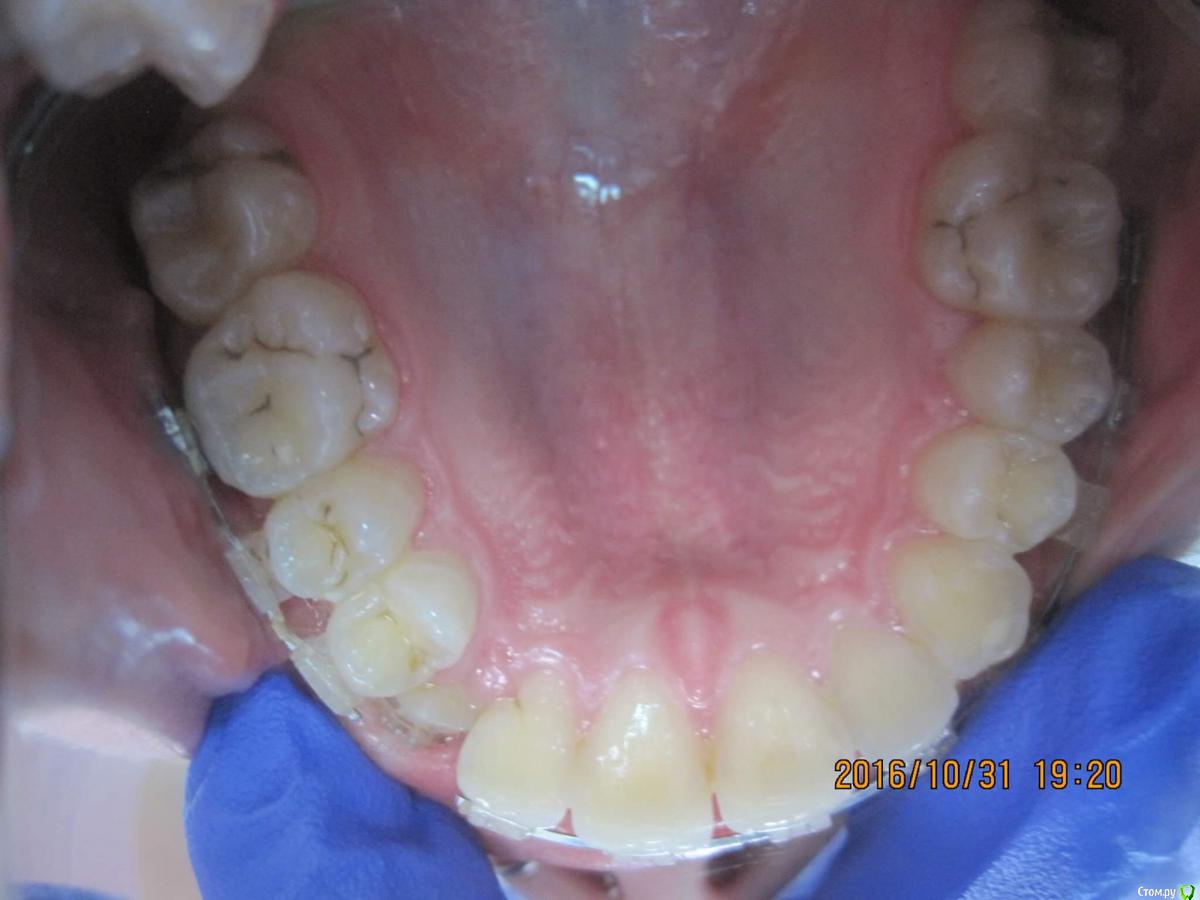

Yana guapa Опубликовано 9 декабря, 2016 Поделиться Опубликовано 9 декабря, 2016 Пытаемся вытянуть 13, но попытки тщетны... хочу знать мнения как поступают в таких ситуациях , если есть заместительная резорбция корня ( анкилоз)? что со средний линией? походу именно с ней и нужно работать. Брекеты на 7ках не стоят.... Опору терять начинаете... надо ставить нормальную полноценную систему, развивать зубные арки, центровать средние линии, создавать место , тянуть и ..... конечно же молиться!)))))) 1 Ссылка на комментарий

simpsons Опубликовано 10 декабря, 2016 Автор Поделиться Опубликовано 10 декабря, 2016 что со средний линией? походу именно с ней и нужно работать. Брекеты на 7ках не стоят.... Опору терять начинаете... надо ставить нормальную полноценную систему, развивать зубные арки, центровать средние линии, создавать место , тянуть и ..... конечно же молиться!)))))) Центральная линия смещена. Спасибо!) Ссылка на комментарий

Yana guapa Опубликовано 10 декабря, 2016 Поделиться Опубликовано 10 декабря, 2016 Центральная линия смещена. Спасибо!)только когда поставите пружину, брекет с двойки снимите! Ссылка на комментарий